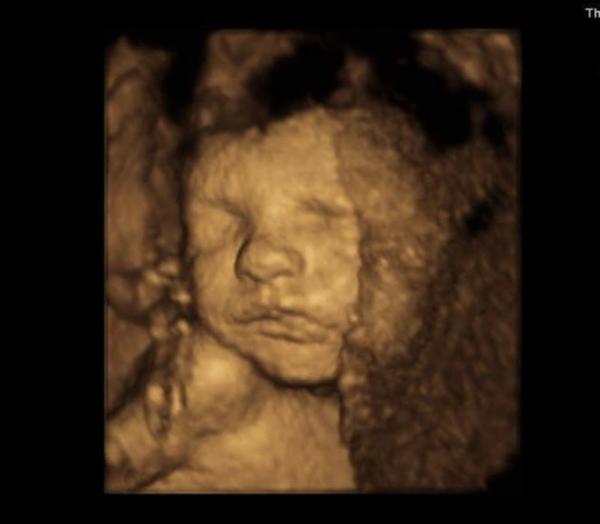

Ve 26-28.tt s obouma synama jsem byla cca v gennetu ☺️A za me parada ..u prvnihu tehu me diky tomu konecne nekdo rekl co čekame 😂